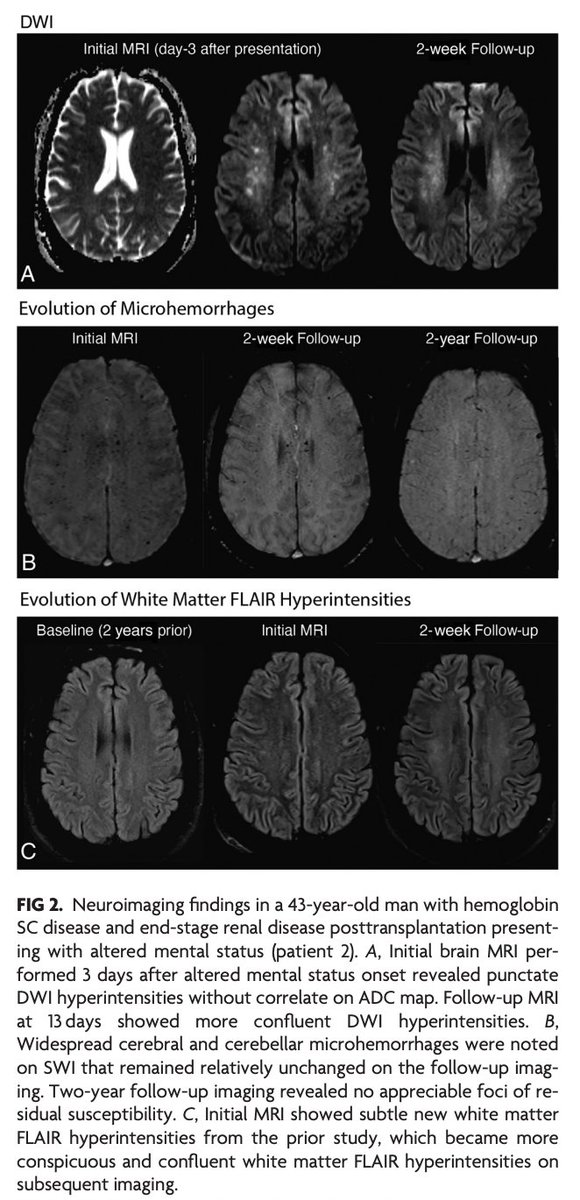

@Rshnzr @HosseiniHelia @zack4186 "CFE in sickle cell–related hemoglobinopathies is more common in complex hemoglobinopathies with otherwise milder disease course and is typically more fulminant compared with traumatic CFE. MRI findings follow a pattern with scattered foci of restricted diffusion, known as the

"Nontrauma-Associated Cerebral Fat Embolism Syndrome in Sickle Cell–Related Hemoglobinopathies: A Case Series and Systematic Review" https://t.co/mjcZ5AQXte

@Rshnzr; @HosseiniHelia; @zack4186

2

13

41